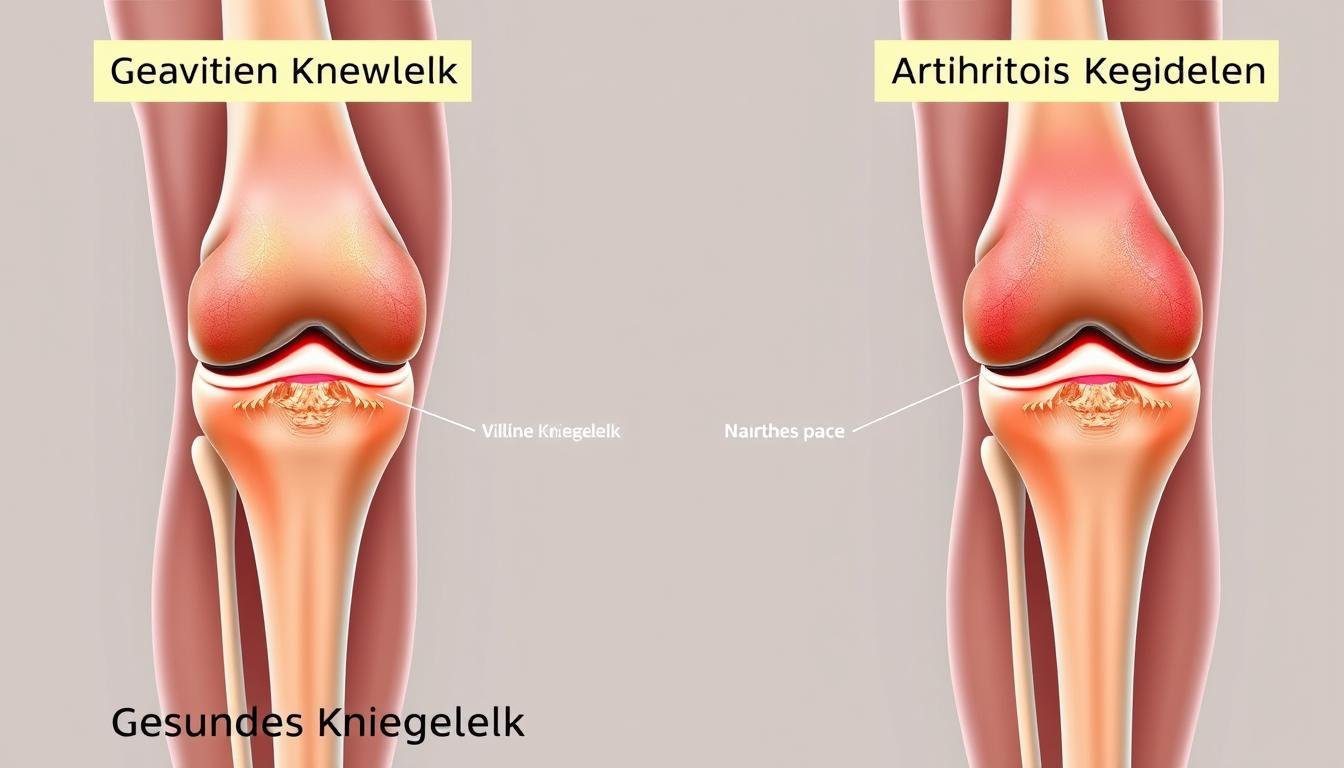

Arten von Kniegelenksprothesen

Je nach Ausmaß der Arthrose und den betroffenen Bereichen des Kniegelenks kommen unterschiedliche Prothesentypen zum Einsatz. Die Wahl des geeigneten Implantats hängt von verschiedenen Faktoren ab, darunter das Alter des Patienten, seine körperliche Aktivität, die Knochenqualität und die spezifische Ausprägung der Arthrose.

Bei der Knie-Totalendoprothese (K-TEP) werden alle Gelenkflächen des Kniegelenks ersetzt. Dies umfasst sowohl die femorale (oberschenkelseitige) als auch die tibiale (schienbeinseitige) Komponente. Die Oberschenkelkomponente besteht aus Metall und ahmt die natürliche Form der Femurkondylen (Oberschenkelrollen) nach. Die Schienbeinkomponente besteht aus einer Metallplatte mit einem Polyethylen-Inlay als Gleitfläche. In manchen Fällen wird auch die Rückfläche der Kniescheibe (Patella) durch eine Kunststoffkomponente ersetzt.

Teilprothese (Schlittenprothese)

Wenn nur ein Bereich des Kniegelenks von Arthrose betroffen ist, kann eine Teilprothese (auch Schlittenprothese oder unikondyläre Prothese genannt) ausreichend sein. Dabei wird nur der geschädigte Teil des Gelenks ersetzt, während die gesunden Bereiche erhalten bleiben. Dies ermöglicht eine natürlichere Kniefunktion und bessere Beweglichkeit.